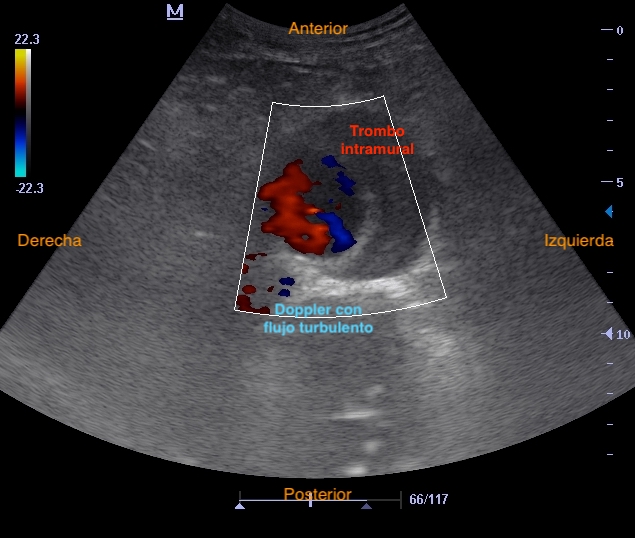

Hallazgos ecográficos

Realizamos eco en consulta donde se aprecia el AAA de 5,6 cm con trombo mural similar a previo, sin signos de rotura.

Aneurisma aórtico abdominal infrarrenal de > 5,5 cm con trombo intramural en su interior.